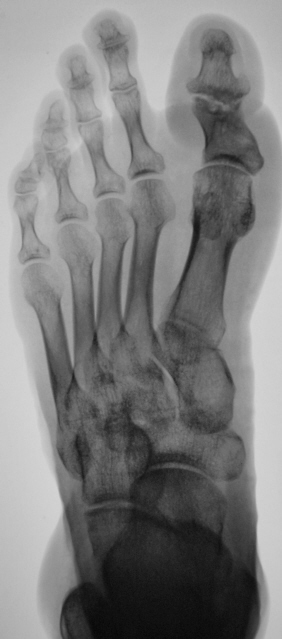

Травма 2 года тому. Пациент направлен хирургом на рентгенографию 1 пальца в связи с усиливающимися болями в области первого пальца. К вечеру боли носят "пекущий" характер (со слов пациента).